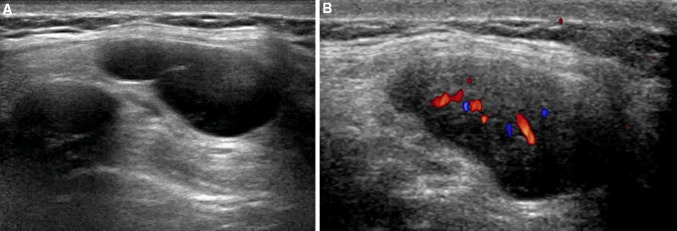

Whereas ultrasound can assess the vascularity of the anomaly (Fig. 14), the type of vessels feeding the lesion, and the presence of a high-flow component, MRI and MRA are excellent methods for depicting the anatomical extent, multicompartmental involvement, and vascular angioarchitecture. Ultrasound is great for follow-up and helps guide interventional therapies. CT is rarely used due to radiation concerns. Digital subtraction angiography (DSA) is usually performed for therapeutic intervention [86].

Fig. 14.

Vascular malformation of the abdominal wall. Ultrasound shows dilated vessels in the subcutaneous tissues (a, b panoramic view). Color Doppler ultrasound confirms the vascular nature of the lesions. RA rectus abdominis, EO external oblique, IO internal oblique, TA transversus abdominis, LA linea alba, LS semilunar line